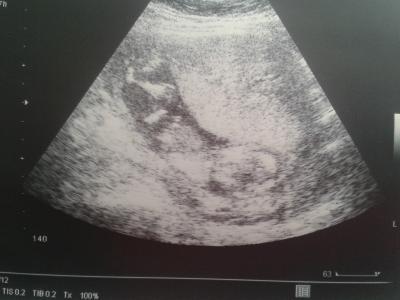

Alles super mit dem baby hat auch schön geschlagen. Man konnte es nicht erkennen das Ultraschall gerät ist alt muss in drei wochen noch mal hin. ..er hat eine vermutung sagt es aber nicht, nicht das ich später enttäuscht bin hehe... Ich glaube aber ein Junge hab was gesehen :)

Bild zu zurück vom Frauenarzt - Forum für August - Mamis

Super das alles gut ist. Oh ja der Ultraschall ist älter, aber man sieht was auf dem bild.